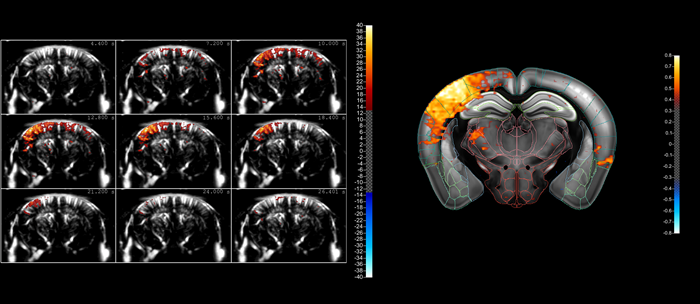

Indicative comparison of the imaging performance that can be achieved using cUS (left) and true fUS (right) for the rat brain (here involving a craniotomy), in both cases carried out by adjusting the scan settings on Iconeus One. fUS clearly has an advantage over cUS in terms of resolution and sensitivity. Image Credit: Iconeus

A typical compiled sequence of images acquired using fUS, showing the ‘lighting up’ of a part of the mouse brain as a result of whisker stimulation. The fact that blood flows in the brain can be in different directions within a small volume means that it’s better to image this activity using blood volume (using Power Doppler) rather than blood velocity (using color Doppler). However, our fUS– and microbubble-enabled ultrasound localization microscopy (ULM) technique – allows the actual blood velocities to be determined at high resolution, should that information be needed. Image Credit: Iconeus